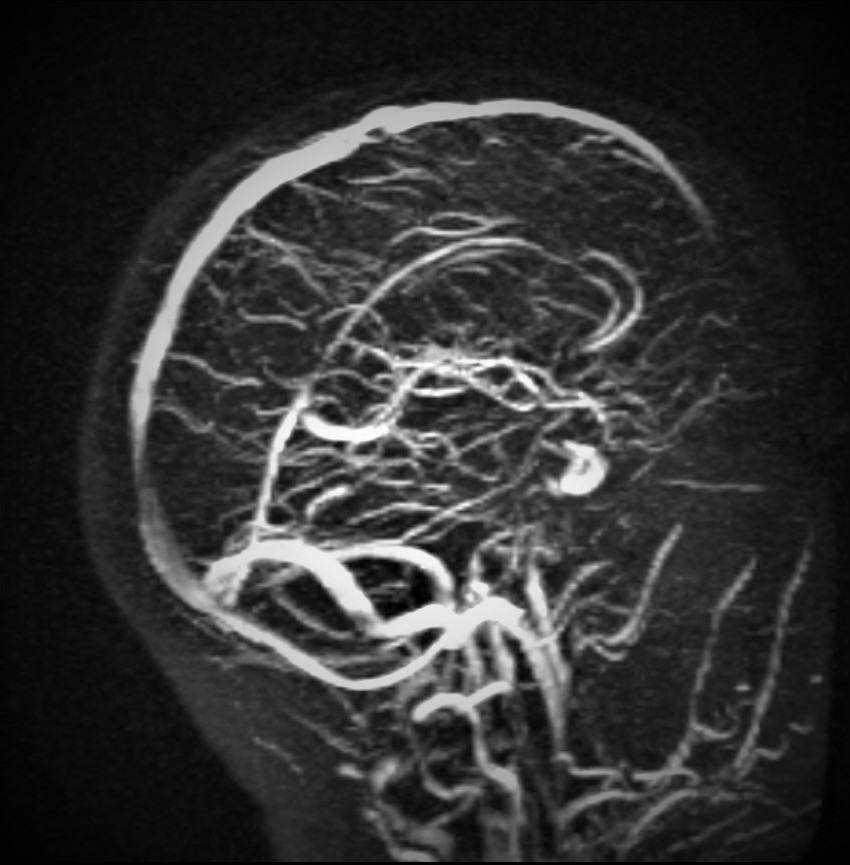

从计算机中恢复的图像。背景未知。